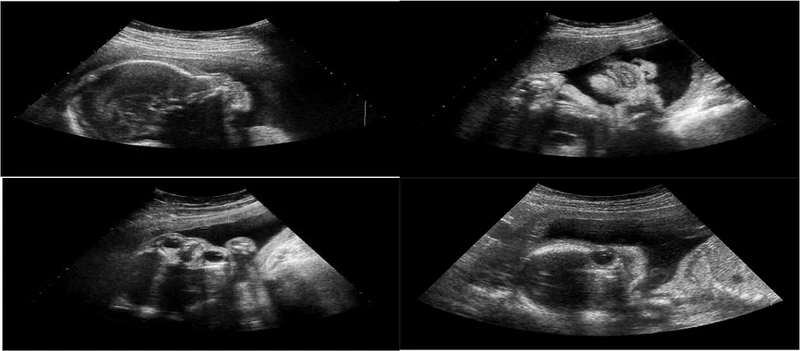

Khoảng thời gian từ 3 đến 5 tuần tuổi là thời điểm lý tưởng để thực hiện siêu âm. Trong giai đoạn này, siêu âm có thể xác định chính xác vị trí của thai nhi trong tử cung, đảm bảo rằng thai đã nằm đúng chỗ. Giấy siêu âm thai nhi 3 tuần tuổi có thể phát hiện sớm những bất thường, chẳng hạn như thai ngoài tử cung hoặc thai ở sẹo mổ cũ. Những phát hiện này là rất quan trọng để bác sĩ có thể đưa ra các biện pháp can thiệp kịp thời và đảm bảo sức khỏe của mẹ và bé.

Giấy siêu âm thai nhi ở giai đoạn 3 tuần tuổi cung cấp những thông tin thiết yếu về sự phát triển và tình trạng của thai kỳ. Trong giai đoạn này, siêu âm giúp xác định vị trí chính xác của thai nhi trong tử cung, điều này rất quan trọng để đảm bảo rằng thai đã nằm đúng chỗ và không gặp phải tình trạng thai ngoài tử cung, một vấn đề có thể gây nguy hiểm cho sức khỏe của người mẹ. Kích thước của túi thai, mặc dù còn nhỏ ở giai đoạn 3 tuần, cũng được đo để theo dõi sự phát triển ban đầu của thai nhi.

Bên cạnh việc xác nhận sự hiện diện của túi thai trong tử cung, siêu âm còn giúp đánh giá tình trạng của niêm mạc tử cung. Niêm mạc tử cung cần phải dày và khỏe mạnh để tạo điều kiện thuận lợi cho sự phát triển của thai nhi. Việc kiểm tra này đảm bảo rằng môi trường trong tử cung là lý tưởng cho sự phát triển của thai, đồng thời giúp phát hiện sớm các vấn đề có thể xảy ra.

Ngoài ra, siêu âm ở giai đoạn 3 tuần tuổi còn có khả năng phát hiện sớm các bất thường như thai ở sẹo mổ cũ từ các ca phẫu thuật trước đây. Điều này rất quan trọng vì các bất thường này có thể yêu cầu can thiệp y tế kịp thời để đảm bảo an toàn cho cả mẹ và bé.

Mặc dù trong giai đoạn này, các chi tiết về cấu trúc của thai nhi chưa rõ ràng, siêu âm vẫn cung cấp thông tin cơ bản về sự phát triển của phôi thai. Những thông tin này giúp bác sĩ theo dõi và đánh giá sức khỏe của thai kỳ, đồng thời cung cấp sự yên tâm cho các bậc cha mẹ trong những tuần đầu của thai kỳ. Nhờ vào siêu âm, các vấn đề tiềm ẩn có thể được phát hiện sớm và điều trị kịp thời, góp phần vào việc đảm bảo một thai kỳ khỏe mạnh và an toàn.